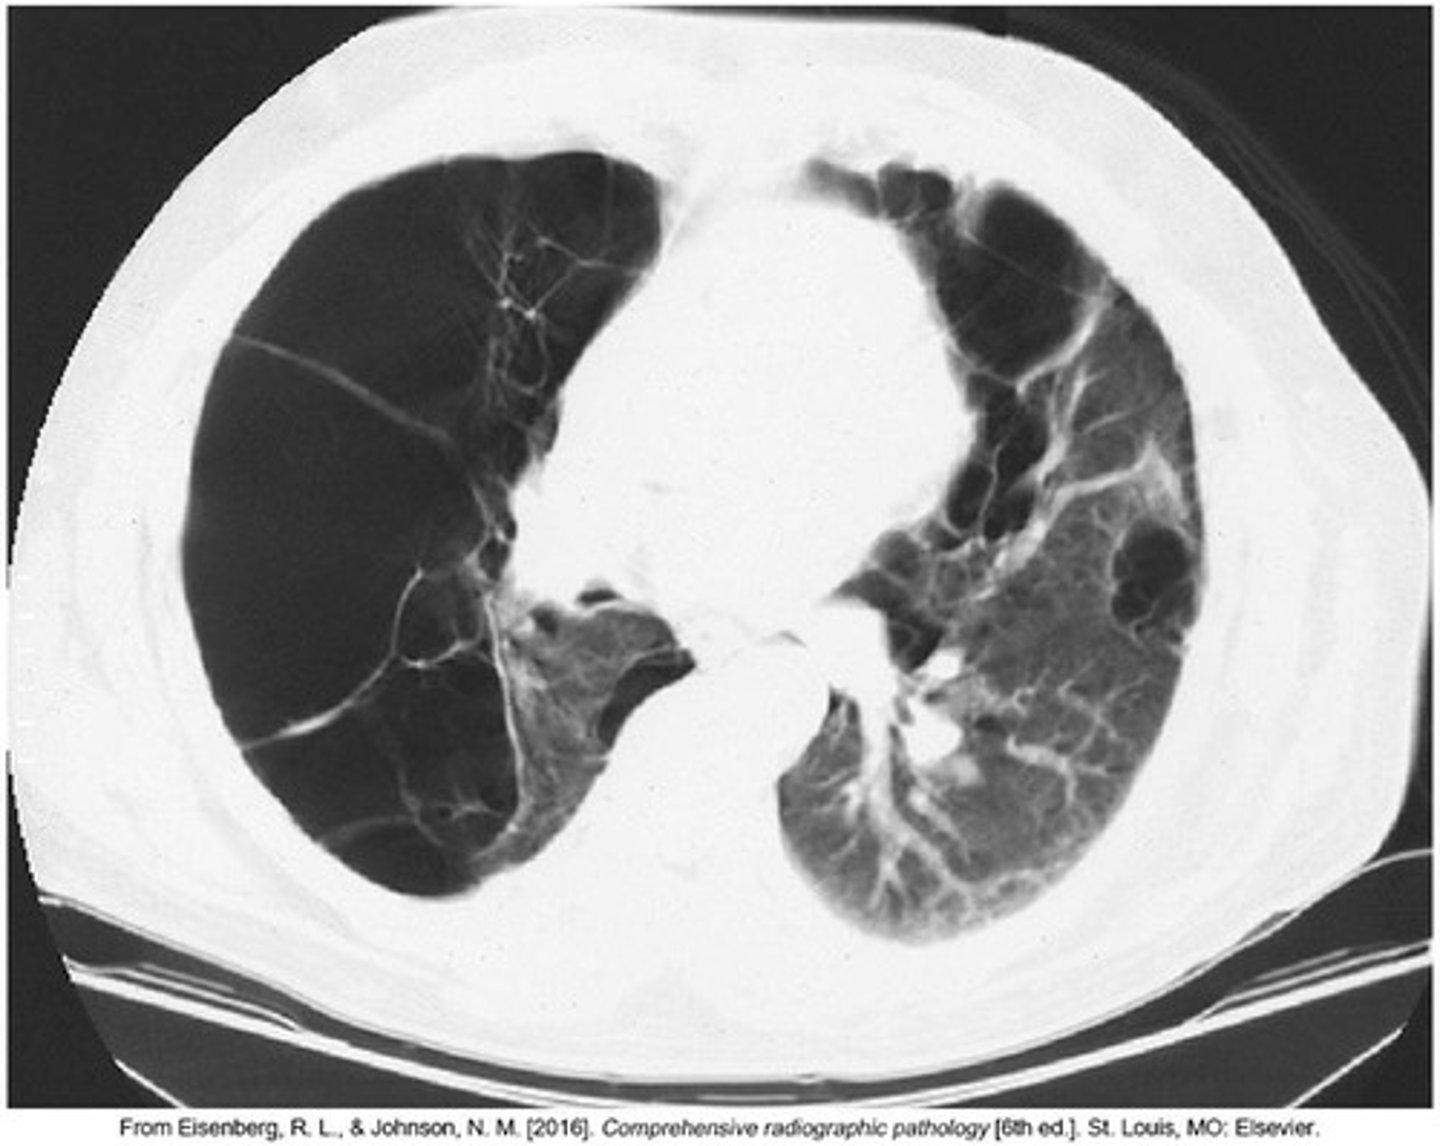

Chest CT

Detailed imaging for assessing lung conditions.